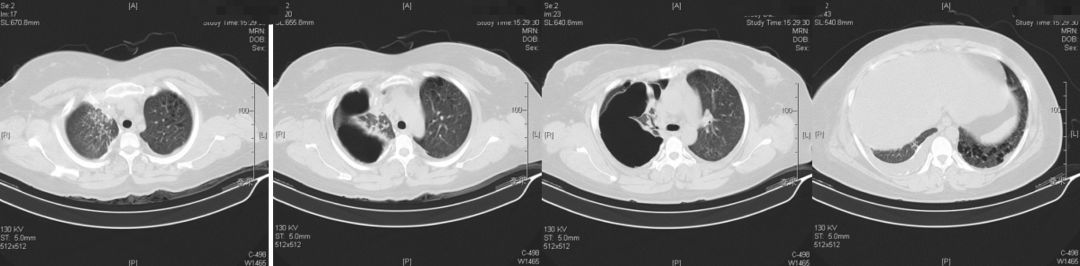

2019-5-14我院胸部CT平扫

患者青年女性,因「咳嗽、咳痰、咯血半月余,胸痛8天」入院,急性起病,逐渐加重,胸部CT提示右侧气胸,双肺相对弥漫分布的气囊与结节,沿气管血管束分布,右下肺实变。肺部弥漫性囊泡样疾病,需要考虑肺淋巴管平滑肌瘤病(LAM)、BHD综合征、肺朗格汉斯组织细胞增生症(PLCH)、淋巴细胞性间质性肺炎(LIP)、感染性疾病如耶氏肺孢子菌肺炎(PCP)等疾病。LAM一般常见于育龄期女性,影像学以弥漫均匀分布的薄壁囊泡为主要表现,此例患者为年轻女性,肺部多发囊泡,需要考虑LAM,但囊泡不是薄壁,分布不均匀,形状不规则,不符合LAM的典型表现。PLCH一般多见于吸烟患者,影像学以奇形怪状的沿支气管血管束分布的囊泡样改变为特点,吸烟患者一般以上叶及中叶病变为主,不累及肋膈角,多系统病变患者可以累及肋膈角,本例需考虑PLCH可能。BHD综合征肺部表现为多发薄壁囊肿,形状不规则,多于基底部、外周、沿纵隔分布,其他系统表现可合并皮疹、肾肿瘤等,可有家族史,本例患者无BHD家族史,需进一步排查其他器官有无病变。LIP常有肺部多发囊泡改变,一般合并自身免疫性疾病,该患者需进一步完善自身抗体等风湿免疫相关指标,协助诊断。此外,还需考虑PCP、金葡菌感染等感染性疾病。PCP多见于免疫抑制宿主,可以有多发性肺气囊的表现,该患者无发热,无免疫抑制病史,目*考前**虑可能性不大。

2019-05-31胸部CT:

放射科张兴伟副主任医师

本例患者的胸部CT主要表现为两肺相对弥漫分布的怪异的气囊和结节,气囊为薄壁,以中上肺分布为主,沿支气管血管束分布,符合LCH细胞沿支气管分布的特点,并且有可能会引起支气管阻塞,类似活瓣样的作用,因此囊腔的形状怪异。胸腔镜术后的CT表现,可能是局部阻塞牵拉引起疱的加重,也可能是胸膜粘连后局限性的气胸的表现。